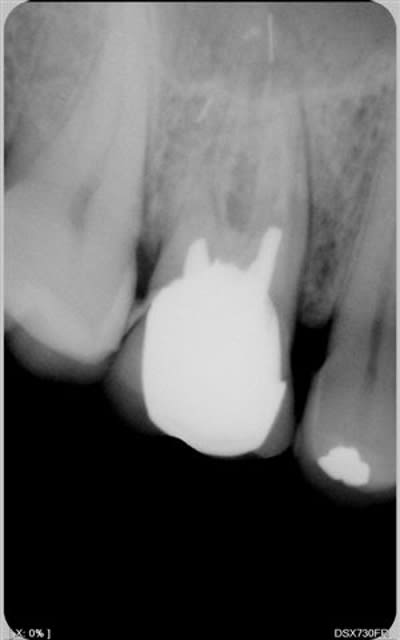

Faut il retirer le fragment ? Je comprends pourquoi il y en a qui font plus de chiffre que d'autres. S'il fallait extraire et mettre un implant chaque fois qu'il y a un instrument cassé... Les canaux tels qu'ils sont ne me paraissent pas spécialement bien obturés, y compris celui qui ne présente pas de morceau d'instrument. Donc reprise pour moi.

d abord une bonne radio....

désolé je n'ai à votre disposition que ces radios, ce sont celles de son praticien traitant. Je n'ai pas vu la patiente et je suis ,comme vous, consulté pour avis d'après radios. Je serais bien tenté de conseiller d'aller voir un endo exclusif, non pas pour essayer de sortir les fragments mais, quitte à tenter, au moins mettre toutes les chances de notre côté.

qquesoit la stratégie conservatrice, je ne comprends pas un retraitement endo, aussi sur soit il, sans éliminer par chir les fragments métalliques....